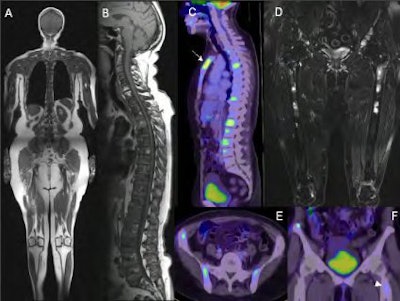

| A 68-year-old woman with breast cancer. A) T1-weighted TSE whole-body MRI at 3 tesla. B) Sagittal T1-weighted TSE sequences reveal infiltration of almost the complete spine. C) PET/CT shows pathological FDG uptake in the larger focal metastases only. A metastasis of the sternum is masked by field saturation and is prone to be missed in peripheral sections of coronal whole-body MRI (arrow). D) Whole-body STIR shows multifocal pelvic metastases and additional infiltration of both distal femurs, an area often not covered by the field of view of the PET/CT scan. E,F) Axial and coronal PET/CT of the pelvis confirms multifocal metastases in both iliac bones. Only faint tracer uptake is observed in a bone metastasis of the left proximal femur (arrowhead). All images courtesy of Dr. Gerwin Schmidt. |

"You need the combined approach -- STIR alone would not work as well," Schmidt said. "The combination of both, even without contrast, is still highly diagnostic for bone metastases, although contrast is vital for organs."